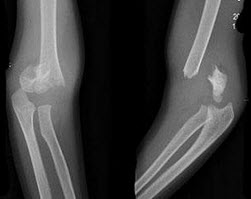

4、单项选择题

男,30岁,右膝关节酸胀,疼痛不适5个月,X线检查如图所示,最可能的诊断是()

A.骨巨细胞瘤

B.骨囊肿

C.骨血管瘤

D.动脉瘤样骨囊肿

E.以上均不正确